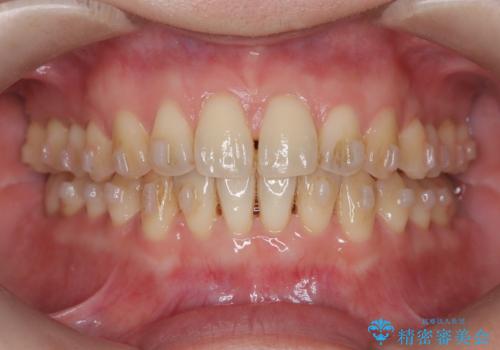

- 「下の前歯が斜めになっている」を主訴に来院された患者様です。

下顎前歯に叢生があり、右上2は反対咬合の状態でした。

下顎前歯の叢生がとれ右上2の反対咬合も改善し患者様にも満足していただけました。治療期間は1年~1年半を見込んでいましたが、患者様の協力もあり10か月で矯正を終えることが出来ました。